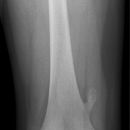

Femurschaftfraktur